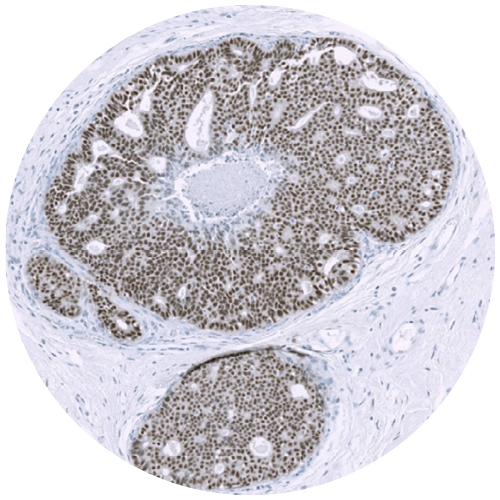

Physical IHC

ViewsML uses deep learning to eliminate physical staining, delivering virtual results in seconds at a fraction of the cost, all the while fitting into existing workflows.

Virtual IHC